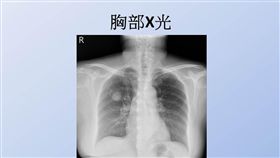

嚇!酷酷嗽三個月 女就醫才知得肺癌

根據衛生福利部統計,國人十大死因排名首位為惡性腫瘤,...